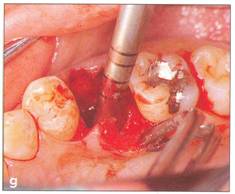

Extraction of the donor tooth If an impacted donor tooth is extracted surgically (see Fi 545e45f g 5-3), alveolar bone over the donor tooth must be removed with a surgical round bur with saline irrigation to avoid damage to the crown or the root. Before elevation of the donor tooth, an incision is made with a blade around the cervical area into the periodontal ligament (see Fi 545e45f g 5-81) to preserve as much periodontal ligament on the root as possible. The extracted donor tooth is immersed in physiologic saline or preservative (see Chapter 3) to prevent drying of the periodontal ligament. The flap of the extraction socket should be closed and sutured to prevent excessive bleeding (see Fi 545e45f g 5-1m). |

Fi 545e45f g 5-4f Extracted second molar, which will be discarded. Fi 545e45f g Extracted donor tooth. The amount of periodontalligament is adequate. Transplantation was performed 6 weeks after extraction of the tooth from the recipient site. Fi 545e45f g 5-4h View of the donor site and preparation of the recipient site. |

Measurement of the donor tooth The size and shape of the donor tooth is determined extraorally to gather information for the preparation of the recipient site. This information is difficult to accurately obtain with preoperative radiographs (see Fi 545e45f gs 5-1h and 580). A caliper or a probe is useful for measuring the mesiodistal or buccolingual width of the crown and the_length 9f the root. The evaluated shape of the root, the length of the root trunk, development of the root (presence of Hertwig's epithelial sheath), and the amount of preserved periodontal ligament should be evaluated and recorded. For these reasons, an extraoral picture of the donor tooth should be taken mesiodistally and buccolingually. |

Evaluation of crown width and try-in The distance between the teeth adjacent to the recipient site (if both are present) must be measured and compared to the mesiodistal width of the donor tooth before the final preparation of the recipient site (see Fi 545e45f g 5-1i). If the donor tooth is too wide, a small amount of enamel can be removed from the proximal surfaces of the adjacent teeth and the donor tooth. In total, no more than 2 mm of enamel should be removed when making these adjustments.2 Orthodontic treatment is sometimes indicated to control the space. |